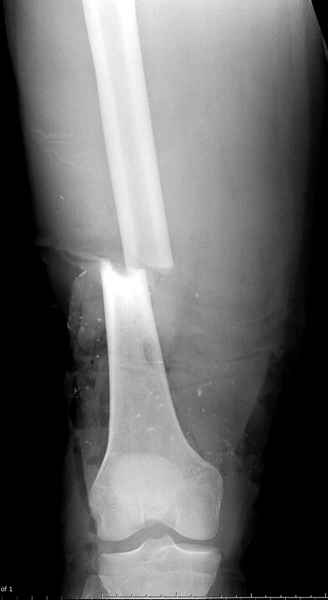

Больному с политравмой установлен наружный "spanning-bridging" фиксатор, после нескольких Irrigation&Debridment на фоне отрицательного посева из раны, через открытый участок установлен 4.5 mm Locking Plate.

На фоне фиксированного перелома бедра мероприятия по восстановлению мягкотканого покрова. Перелом голени зафиксирован после стабилизации бедра традиционным методом.